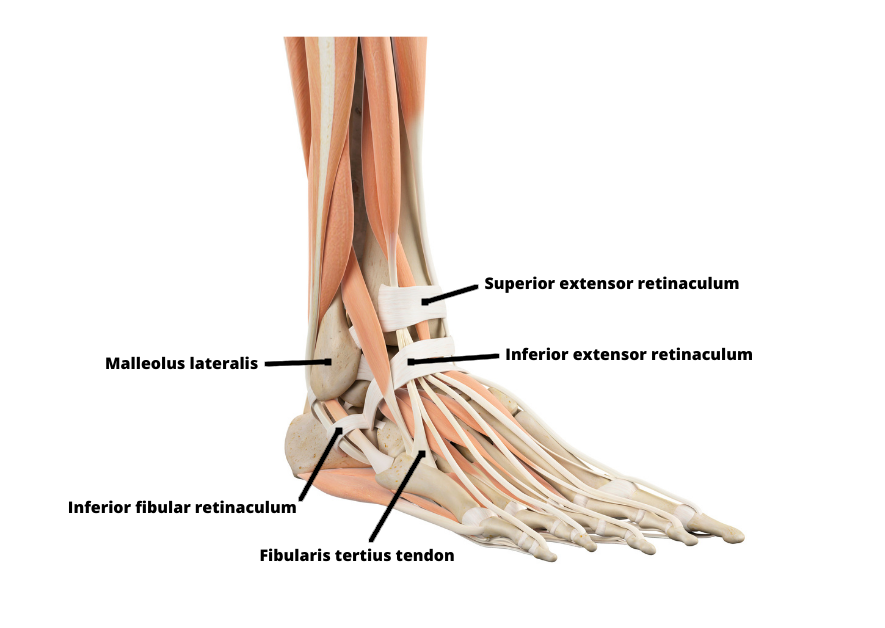

Benskador